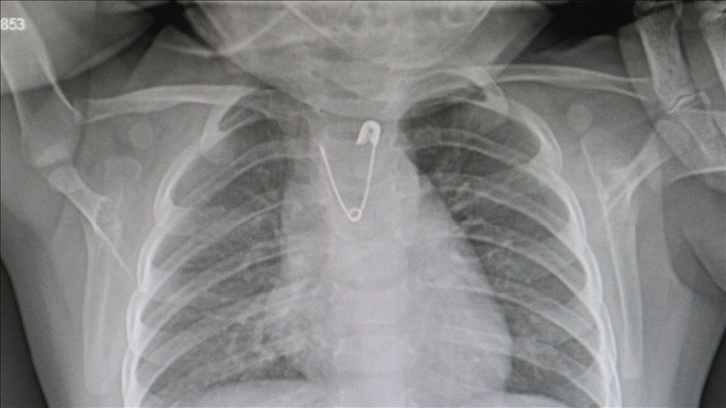

Ankara'da, yakasında bulunan çengelli iğneyi ucu açık bir şekilde yutan 10 aylık kız bebek, getirildiği Ankara Eğitim ve Araştırma Hastanesinde yapılan operasyonla kurtarıldı.